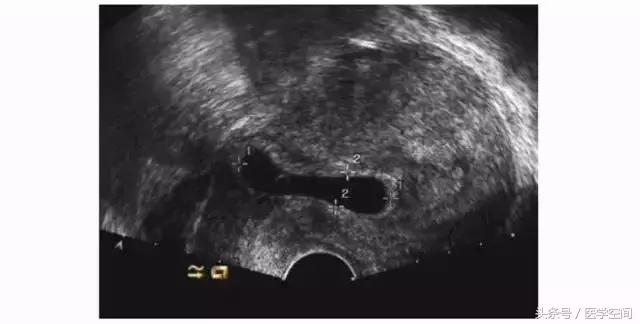

3.1CSP超声漏诊的原因及临床后果

孕囊部分着床于剖宫产子宫瘢痕处而孕囊主要位于宫腔内的不典型CSP(见图4)易被忽略,这类CSP常常被当成了正常宫内早孕,有出血症状时会被认为是先兆流产,对这类患者进行药物流产或人工流产常会导致阴道淋漓出血或大出血需急诊手术干预治疗,有时不得不切除子宫。

图4不典型CSP的超声表现